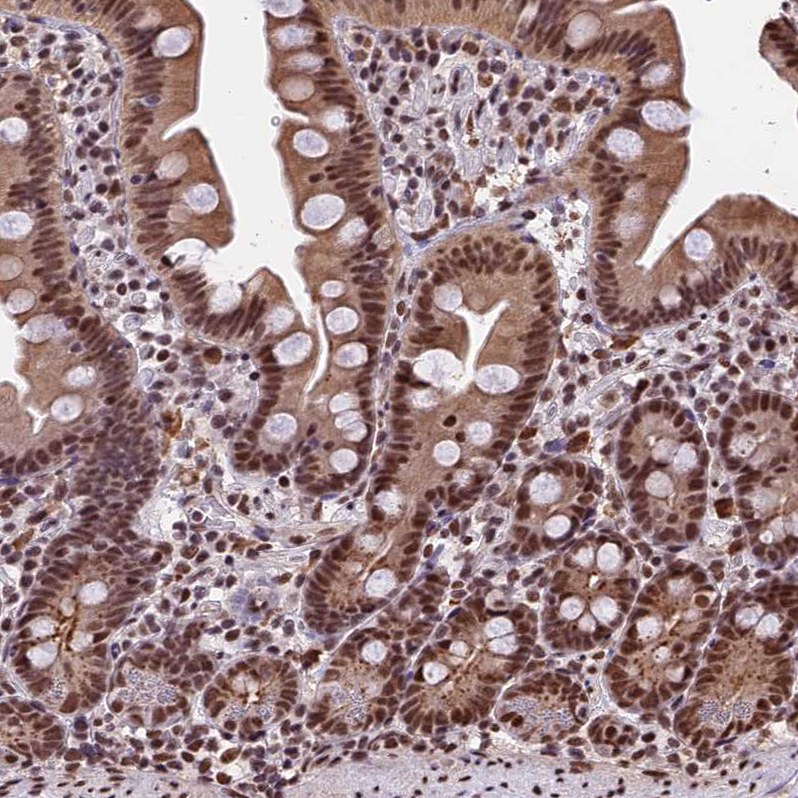

Immunohistochemical staining of human Testis shows strong nuclear and cytoplasmic positivity in cells in seminiferous ducts and Leydig cells.